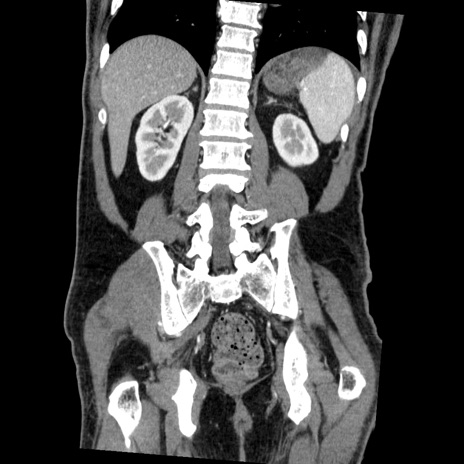

症例22(冠状断像)

【症例】50歳代男性

【主訴】腹痛

【現病歴】AVMからの被殻出血のため回復期リハ病棟入院中。 本日午後3時頃急に下腹部痛が出現した。

【既往歴】AVM、被殻出血、虫垂炎、高血圧

【身体所見】意識晴明、左半身不全麻痺、会話の理解は良好、36.5°C、腹部:膨隆、全体に板状硬、下腹部正中に圧痛点あり、反跳痛-、筋性防御不明、右下腹部にope scar

【データ】WBC 9400、CRP 0.06